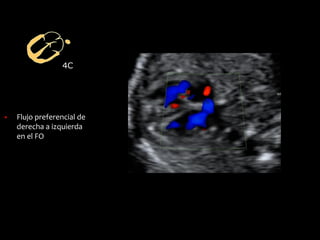

▪ Flujo preferencial de

derecha a izquierda

en el FO